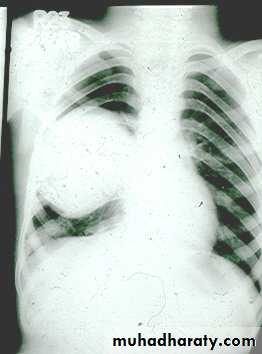

1- Pneumonia.(a) Lobar ( consolidation) pn.

Lobar pneumonia with bronchogram.